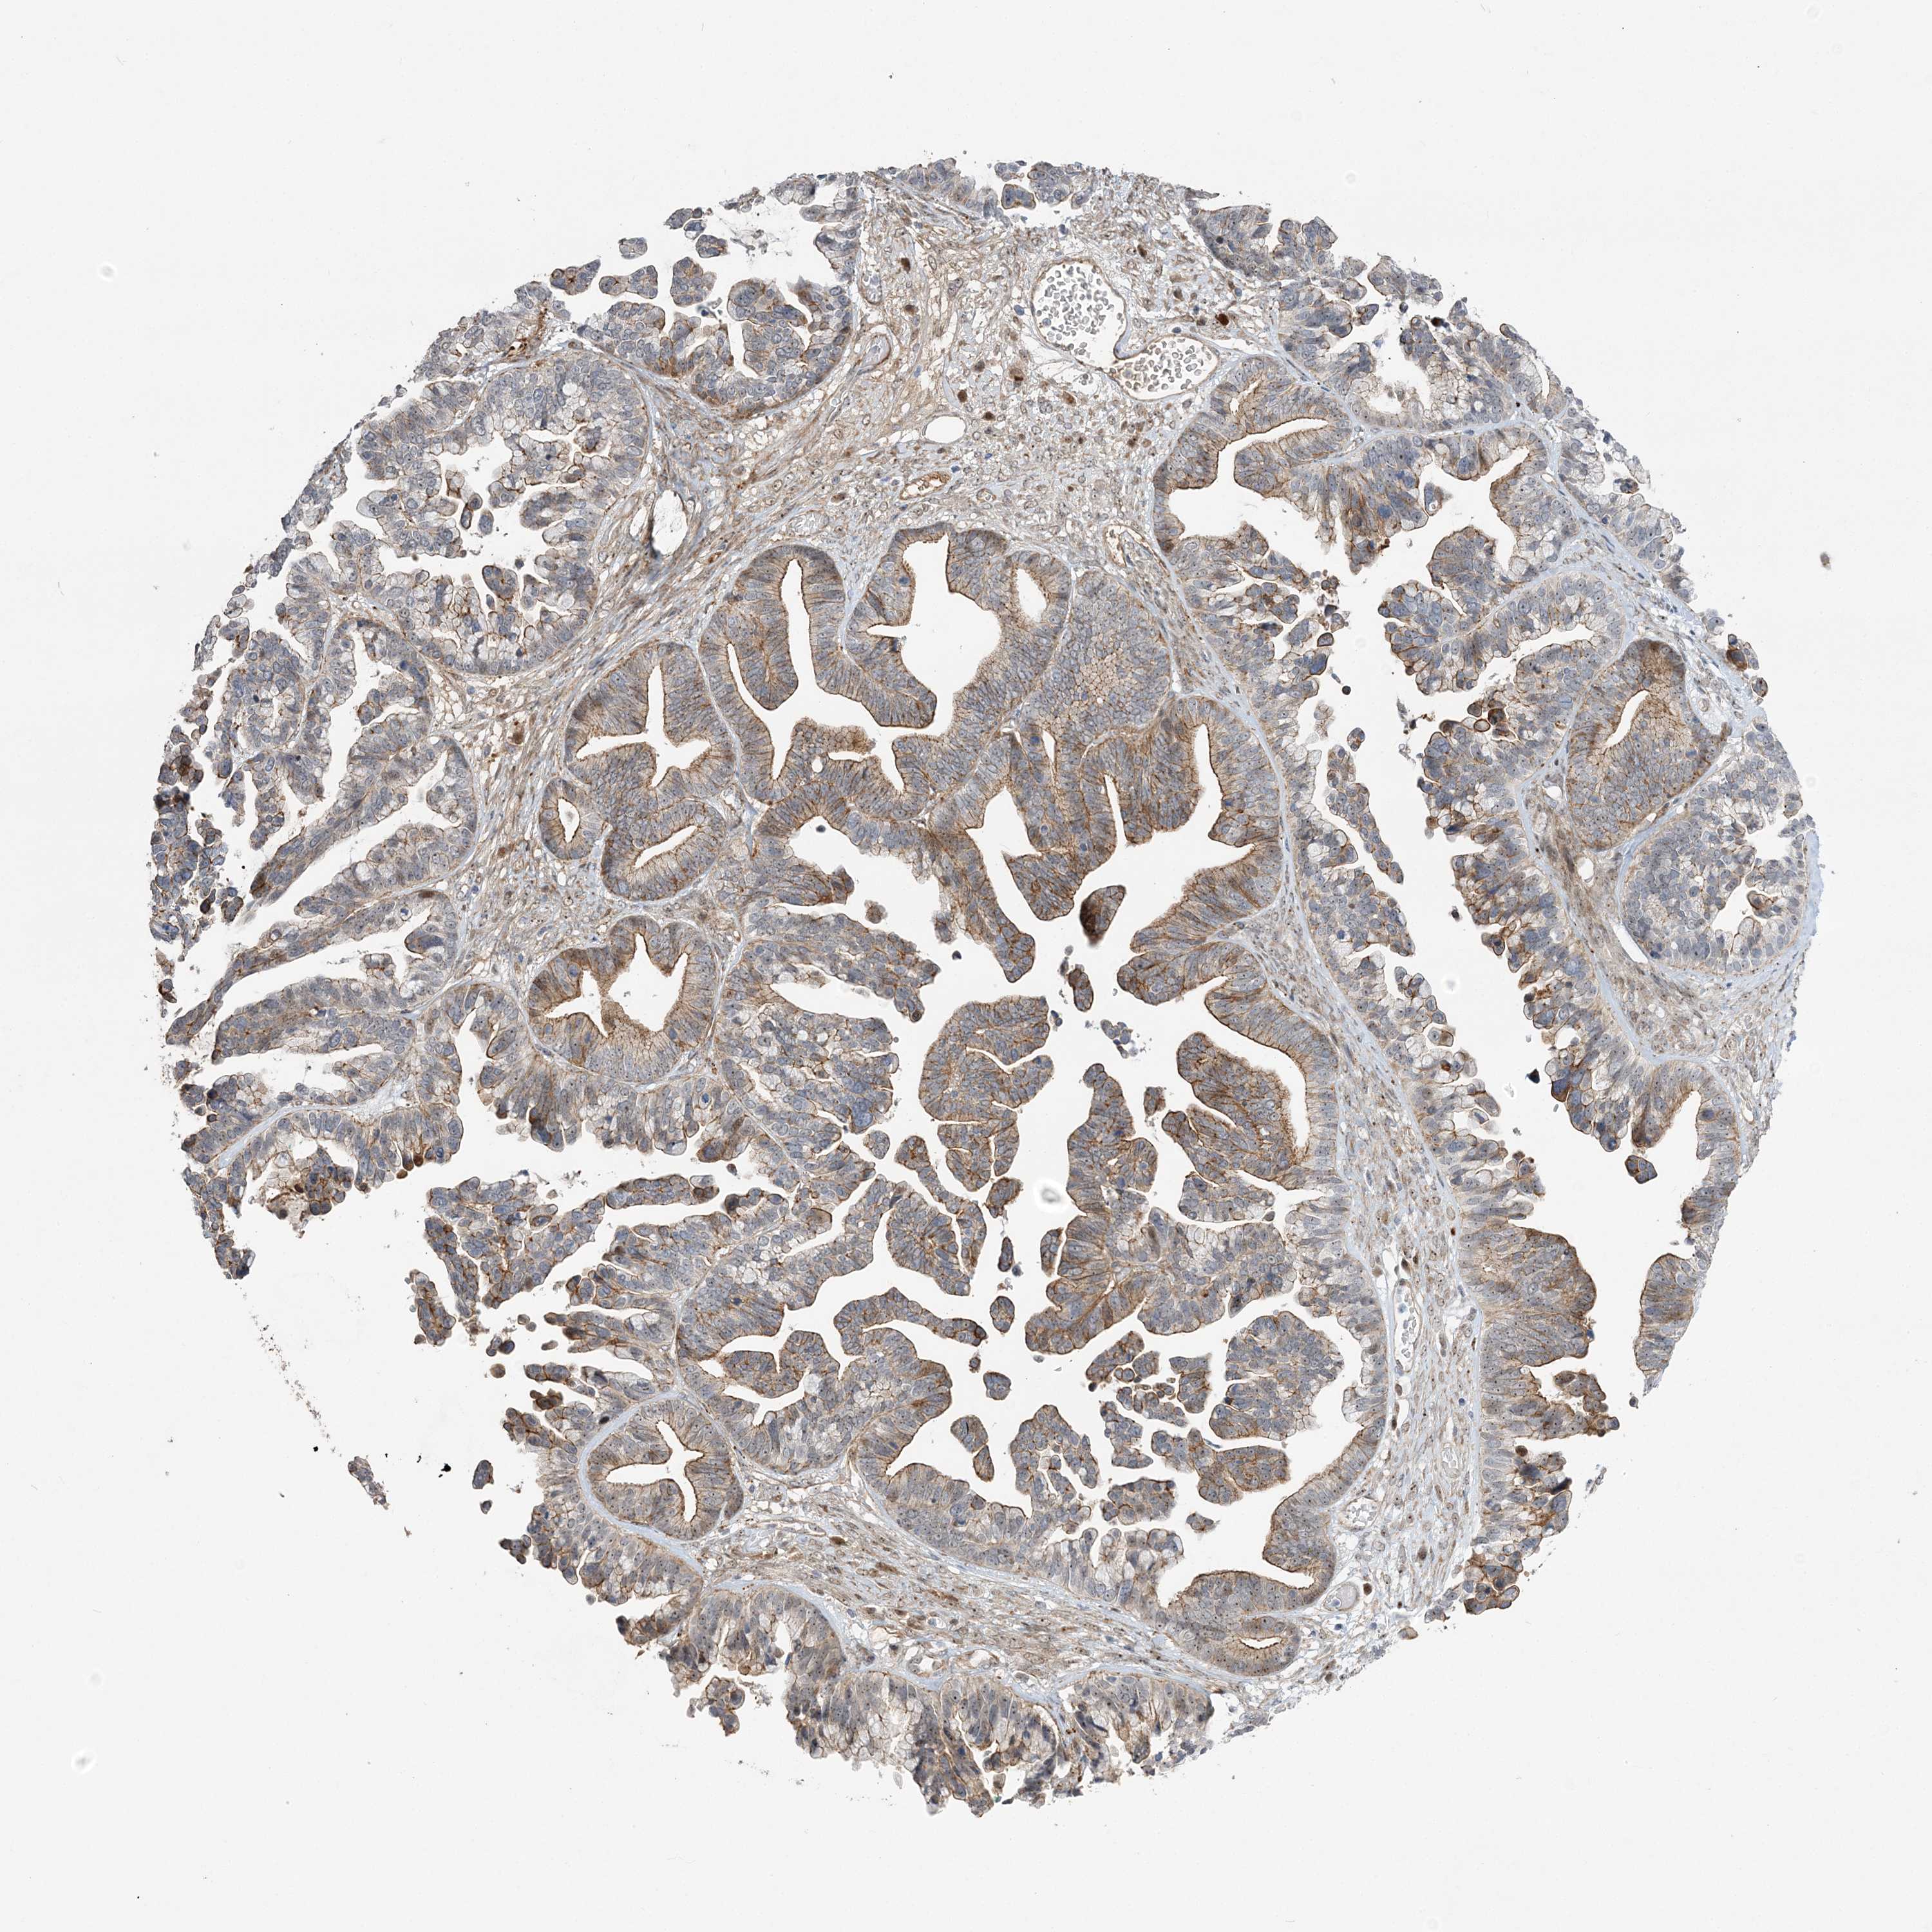

OVARIAN CANCER - Protein expressioni

A mouse-over function shows sample information and annotation data. Click on an image to view it in a full screen mode. Samples can be filtered based on level of antibody staining by selecting one or several of the following categories: high, medium, low and not detected. The assay and annotation is described here.

Note that samples used for immunohistochemistry by the Human Protein Atlas do not correspond to samples in the TCGA dataset.

Antibody stainingi

Antibody staining in the annotated cell types in the current human tissue is reported as not detected, low, medium, or high, based on conventional immunohistochemistry profiling in selected tissues. This score is based on the combination of the staining intensity and fraction of stained cells.

Each image is clickable and will lead to virtual microscopy that enables deeper exploration of all samples and also displays staining intensity scores, fraction scores and subcellular localization as well as patient and tissue information for each sample.

Antibody HPA036295

Antibody HPA036296

Staining

High

Medium

Low

Not detected

Intensity

Strong

Moderate

Weak

Negative

Quantity

>75%

75%-25%

<25%

None

Location

Nuclear

Cytoplasmic/membranous

Cytoplasmic/membranous,nuclear

Cystadenocarcinoma, serous, NOS

Carcinoma, endometroid

Cystadenocarcinoma, mucinous, NOS

Carcinoma, NOS